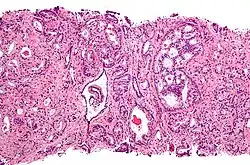

Микрофотография аденокарциномы простаты — наиболее распространённого вида рака предстательной железы.

Для развития и целостного функционирования предстательная железа нуждается в андрогенах. Врождённая дисфункция андрогенового рецептора или 5-альфа-редуктазы у мужчин приводит либо к полному отсутствию, либо лишь к минимальному развитию предстательной железы. То же самое верно и для самцов других животных. Через неделю после кастрации предстательная железа самца крысы подвергается дегенерации из-за апоптоза эпителиальных клеток (после удаления семенников уровень андрогенов недостаточен для поддержания целостности простаты). Андрогены также относятся к факторам, стимулирующим развитие рака предстательной железы. Изучение евнухоидных индивидуумов показало, что у них простата остаётся маленькой и не подвергается гипертрофии или злокачественному перерождению. Более того, в животных моделях канцерогенеза в предстательной железе необходимо наличие семенников или экзогенных андрогенов для поддержания развития опухоли. У трансгенных мышей с повышенной экспрессией AR в простате клетки эпителия простаты обновляются гораздо быстрее, чем в норме, и простатическая интраэпителиальная неоплазия (злокачественное новообразование) у таких мышей появляется значительно раньше. Хотя необходимость андрогенов для развития рака простаты не вызывает сомнений, сложно установить связь между относительным уровнем андрогенов в крови и риском развития рака простаты. Для объяснения различий в частоте возникновения и степени выраженности рака простаты были предложены расовые различия в уровне циркулирующих в крови андрогенов. Впрочем, данные по связи между уровнем андрогенов в крови и риском развития рака предстательной железы весьма противоречивы, и окончательного решения по этому вопросу нет. Возможно, противоречивость данных объясняется варьирующей активностью андрогеновых рецепторов, которая может играть исключительно важную роль в развитии рака простаты[10].